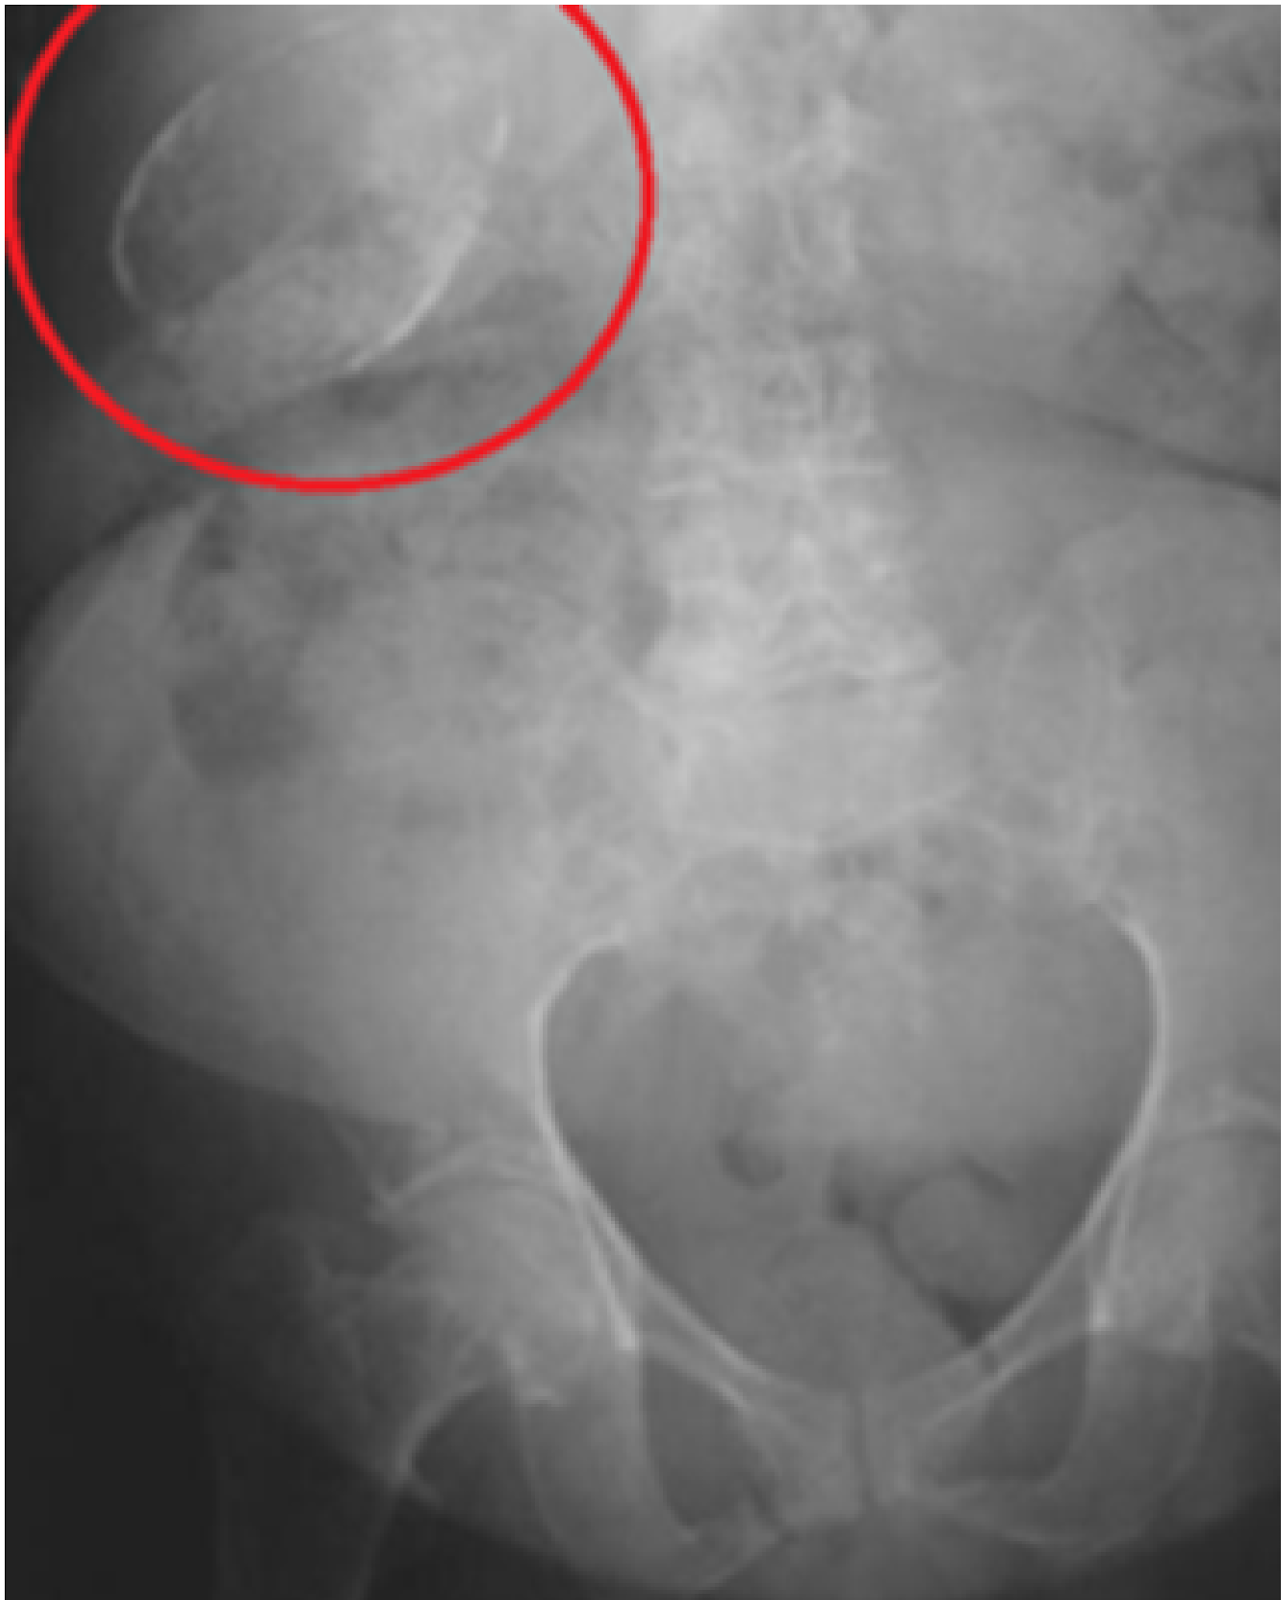

From www.researchgate.net

Porcelain gallbladder. Ultrasound image showing contracted gallbladder What Is A Porcelain Gallbladder Porcelain gallbladder is associated with an increased risk for gallbladder cancer, but the magnitude of risk appears to be small. The wall becomes brittle, hard, and often takes on a bluish hue. Porcelain gallbladder is a rare condition characterized by complete or scattered encrustation of the gallbladder wall. Learn about porcelain gallbladder, a condition characterized by the calcification of the. What Is A Porcelain Gallbladder.